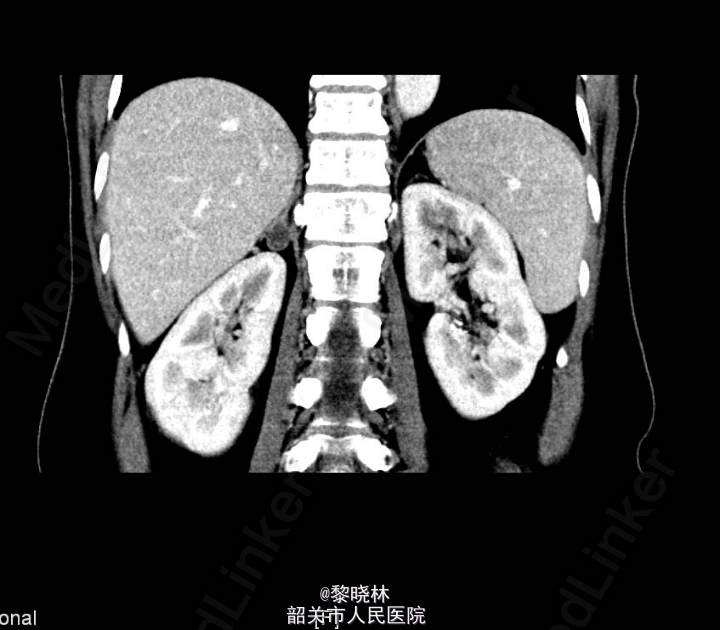

入院查体:BP182/111mmHg,余无特殊。辅助检查门诊CT示双肾+肾上腺螺旋CT平扫+增强扫描(中腹)检查所见:1、右肾上腺结节,考虑腺瘤;左肾上腺增生。2、左肾下盏结石。3、小副脾。

诊断:高血压查因:肾上腺瘤?

入院后查尿蛋白定量/尿肌酐比值 尿总蛋白0.030g/L,尿肌酐4019.000umol/L。高血压三项 醛固酮547.930pg/ml,肾素浓度23.520pg/ml,血管紧张素II137.070pg/ml。 血清钾、钠、氯测定 钾2.930mmol/L。血常规、尿常规、大便常规、生化、甲功、肿瘤标志物、胸片、心电图均未见明显异常。排除手术禁忌症后,于2015-03-16行右侧后腹腔镜下肾上腺肿物切除术,术后病理提示“右侧肾上腺皮质腺瘤”。